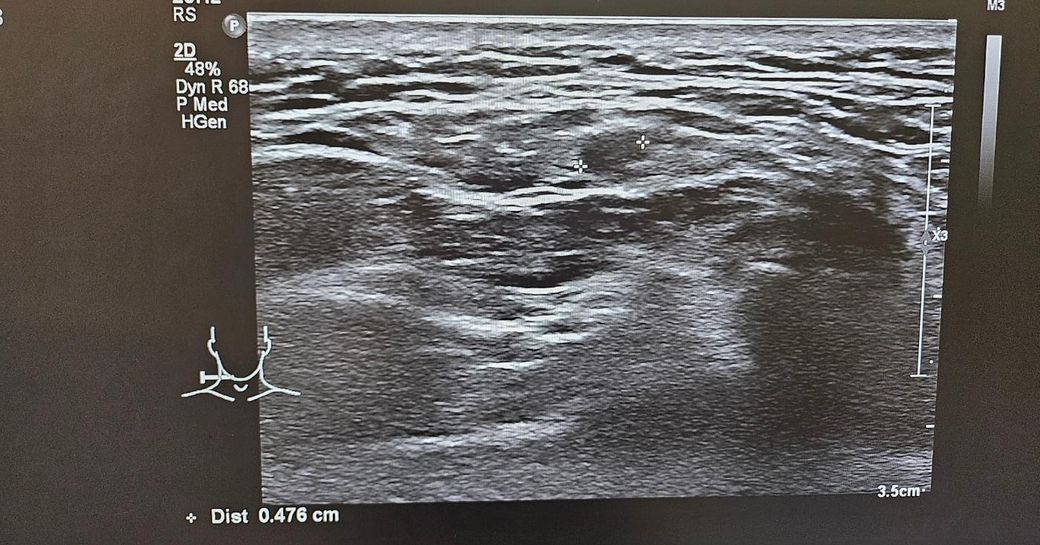

경부초음파 자세하게 설명좀 부탁드립니다

통증이있어서 초음파했는데

약먹고 통증은 없습니다

초음파 보시고 자세히 설명좀 부탁드립니다..

• 3번 째 사진